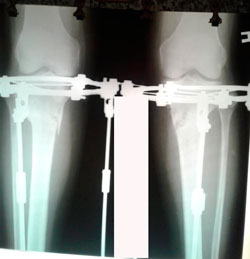

Исходник 38 лет.

Дата операции - 16.03.2020